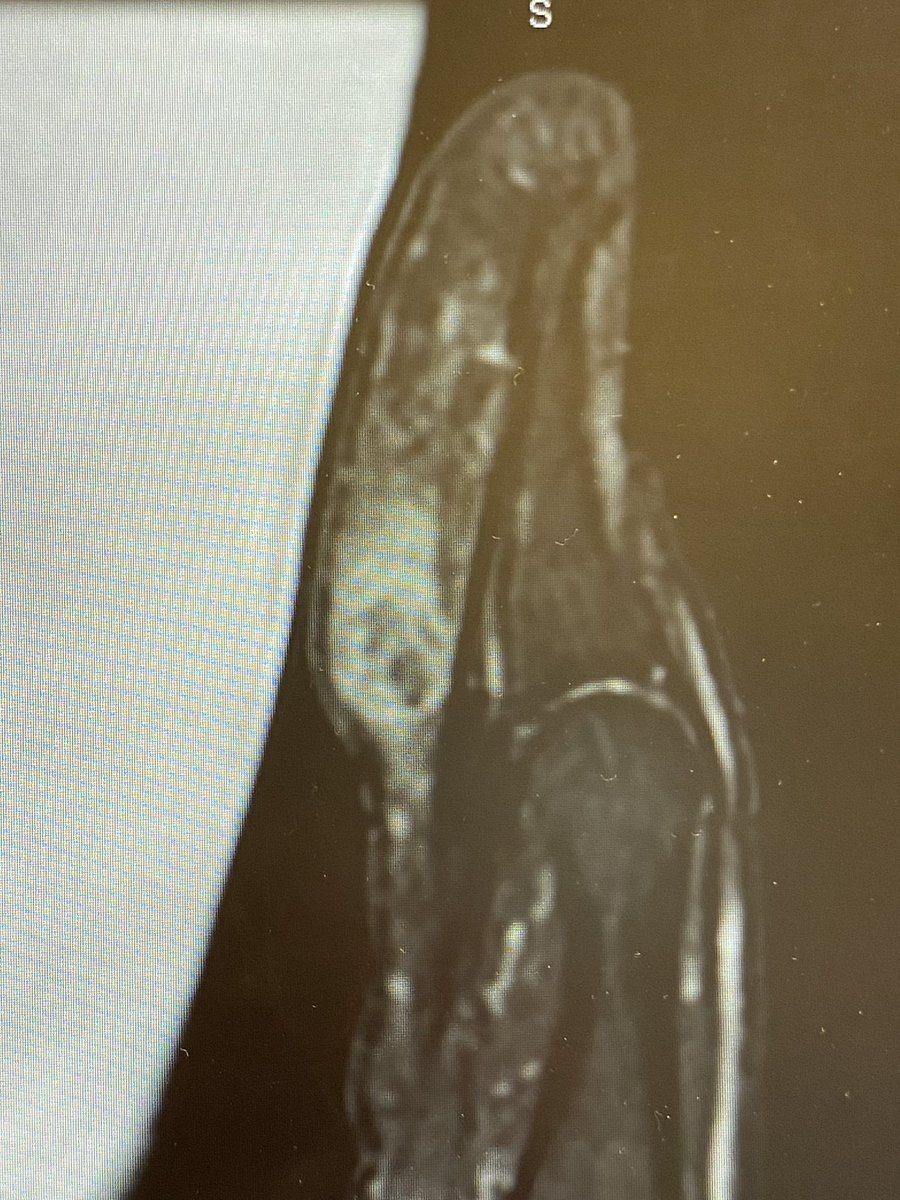

Tender lump in 45 year old thumb pulp - no trauma - no night pain - MR shown with his consent - looks a bit like ��The Scream” - several copies were made in oil and crayon by Munch.

Unexpected